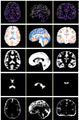

- Project week (Boston, 2010): We have 1) extended HAMMER registration algorithm to work on intensity image, bypassing the pre-segment of MR images; 2) replacing the gaussian propagation with the thin-plate interpolation to achieve more accurate and efficient registration; 3) implement the soft-assignment strategy, instead of the one-to-one correspondence, in detecting correspondence during registration.